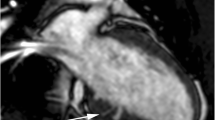

Even if cardiac magnetic resonance (CMR) ability, in the assessment of HCM, is improving [6], especially for intra-myocardial fibrous tissue or scar detection using delayed-enhancement imaging, echocardiography remains the principal tool for the diagnosis and morphological characterization of HCM.

However, since 2009 Maron MS [6] supported an emerging role for CMR in the contemporary evaluation of patients with HCM.

Apical HCM shows a predominant apical distribution of hypertrophy. Myocardial delayed enhancement is seen in the LV apex at the site of maximal hypertrophy in this example.

LV apical aneurysm may be defined as a discrete thin-walled dyskinetic or akinetic segment of the most distal portion of the chamber with a relatively wide communication to the LV cavity [52]. The incidence of concealed apical aneurysm with mid-ventricular cavity obliteration is approximately 1–2 % of all HCM cases [18]. The echocardiographic assessment of the aneurism should include: size (max length or width), dyskinetic/akinetic pattern, thin rims and transmural (and often more extensive) myocardial scarring identified by late gadolinium enhancement on CMR. Specific complications are more common in association with large or medium rather than with small aneurysms and they consist of: sudden death, LV systolic dysfunction, progressive heart failure symptoms, embolic stroke by LV apical thrombus [16, 17–52].

Diagnostic accuracy for LV apical aneurysm is 57 % for echocardiography (more for medium/large in just 2 dimensions provided by 2D-aneurism), 80 % for echocardiography with the use of a contrast agents (Fig. 4E) and 100 % for CMR [53].

In 2009, Maron MS et al. [6], using Cardiac Magnetic Resonance (CMR), concluded that patterns of LV hypertrophy are usually not extensive in HCM, involving <50 % of the chamber in about one-half the patients, and are particularly limited in extent in an important minority. Contiguous portions of anterior free wall and septum constituted the predominant region of wall thickening, with implications for clinical diagnosis [6].